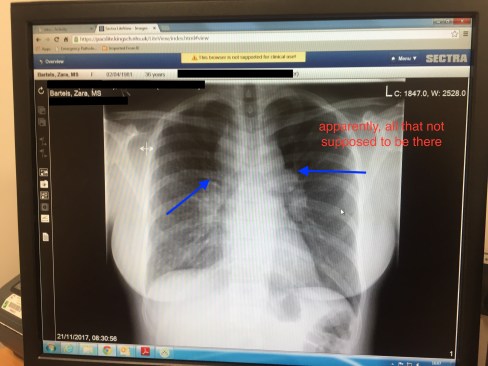

Then @ 8:50am the lovely good looking Isiah made everything a little more concerning. He asked me to stick around and started asking me a bunch of questions and after trying to be slick, I got him to eventually admit to me that, âMy Chest X-ray is concerning, and I need to go to my GP 1st thing tomorrow to discuss the resultsâ

Fuck me! So not a straightforwardâ chest x-ray, not a simple case of a really bad chest infection. But you know I’m on a mission, cause I canât tell my mother I quit another job this year without having sorted another, so I have interviews to get my ass tooâ.

âYour chest x-ray isnât good. We have to do more tests to fully diagnose, but itâs 1 of 3 things –

Lung cancer [WTF?!?!],

Lymphoma [this woman crazy!?!?] or

Sarcoidosis [I know she crazy cause only people on House or Greysâ Anatomy have that, and those are TV shows].

Your heart rate is 160 – itâs working too hard and your lymph nodes are inflamed around 400%â